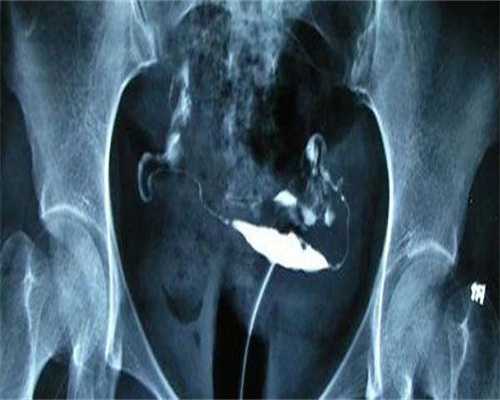

取卵很痛,莉莉每次回忆起取卵的过程都觉得不堪回首,即使打了麻药,可是那种疼痛也能明显的感觉到。医生一共取了莉莉10颗卵子,还取了莉莉老公的一些精子,然后就开始培养受精卵,然后就开始进行移植。移植之后还要吃黄体酮,莉莉吃过药之后总是出现不适症状。